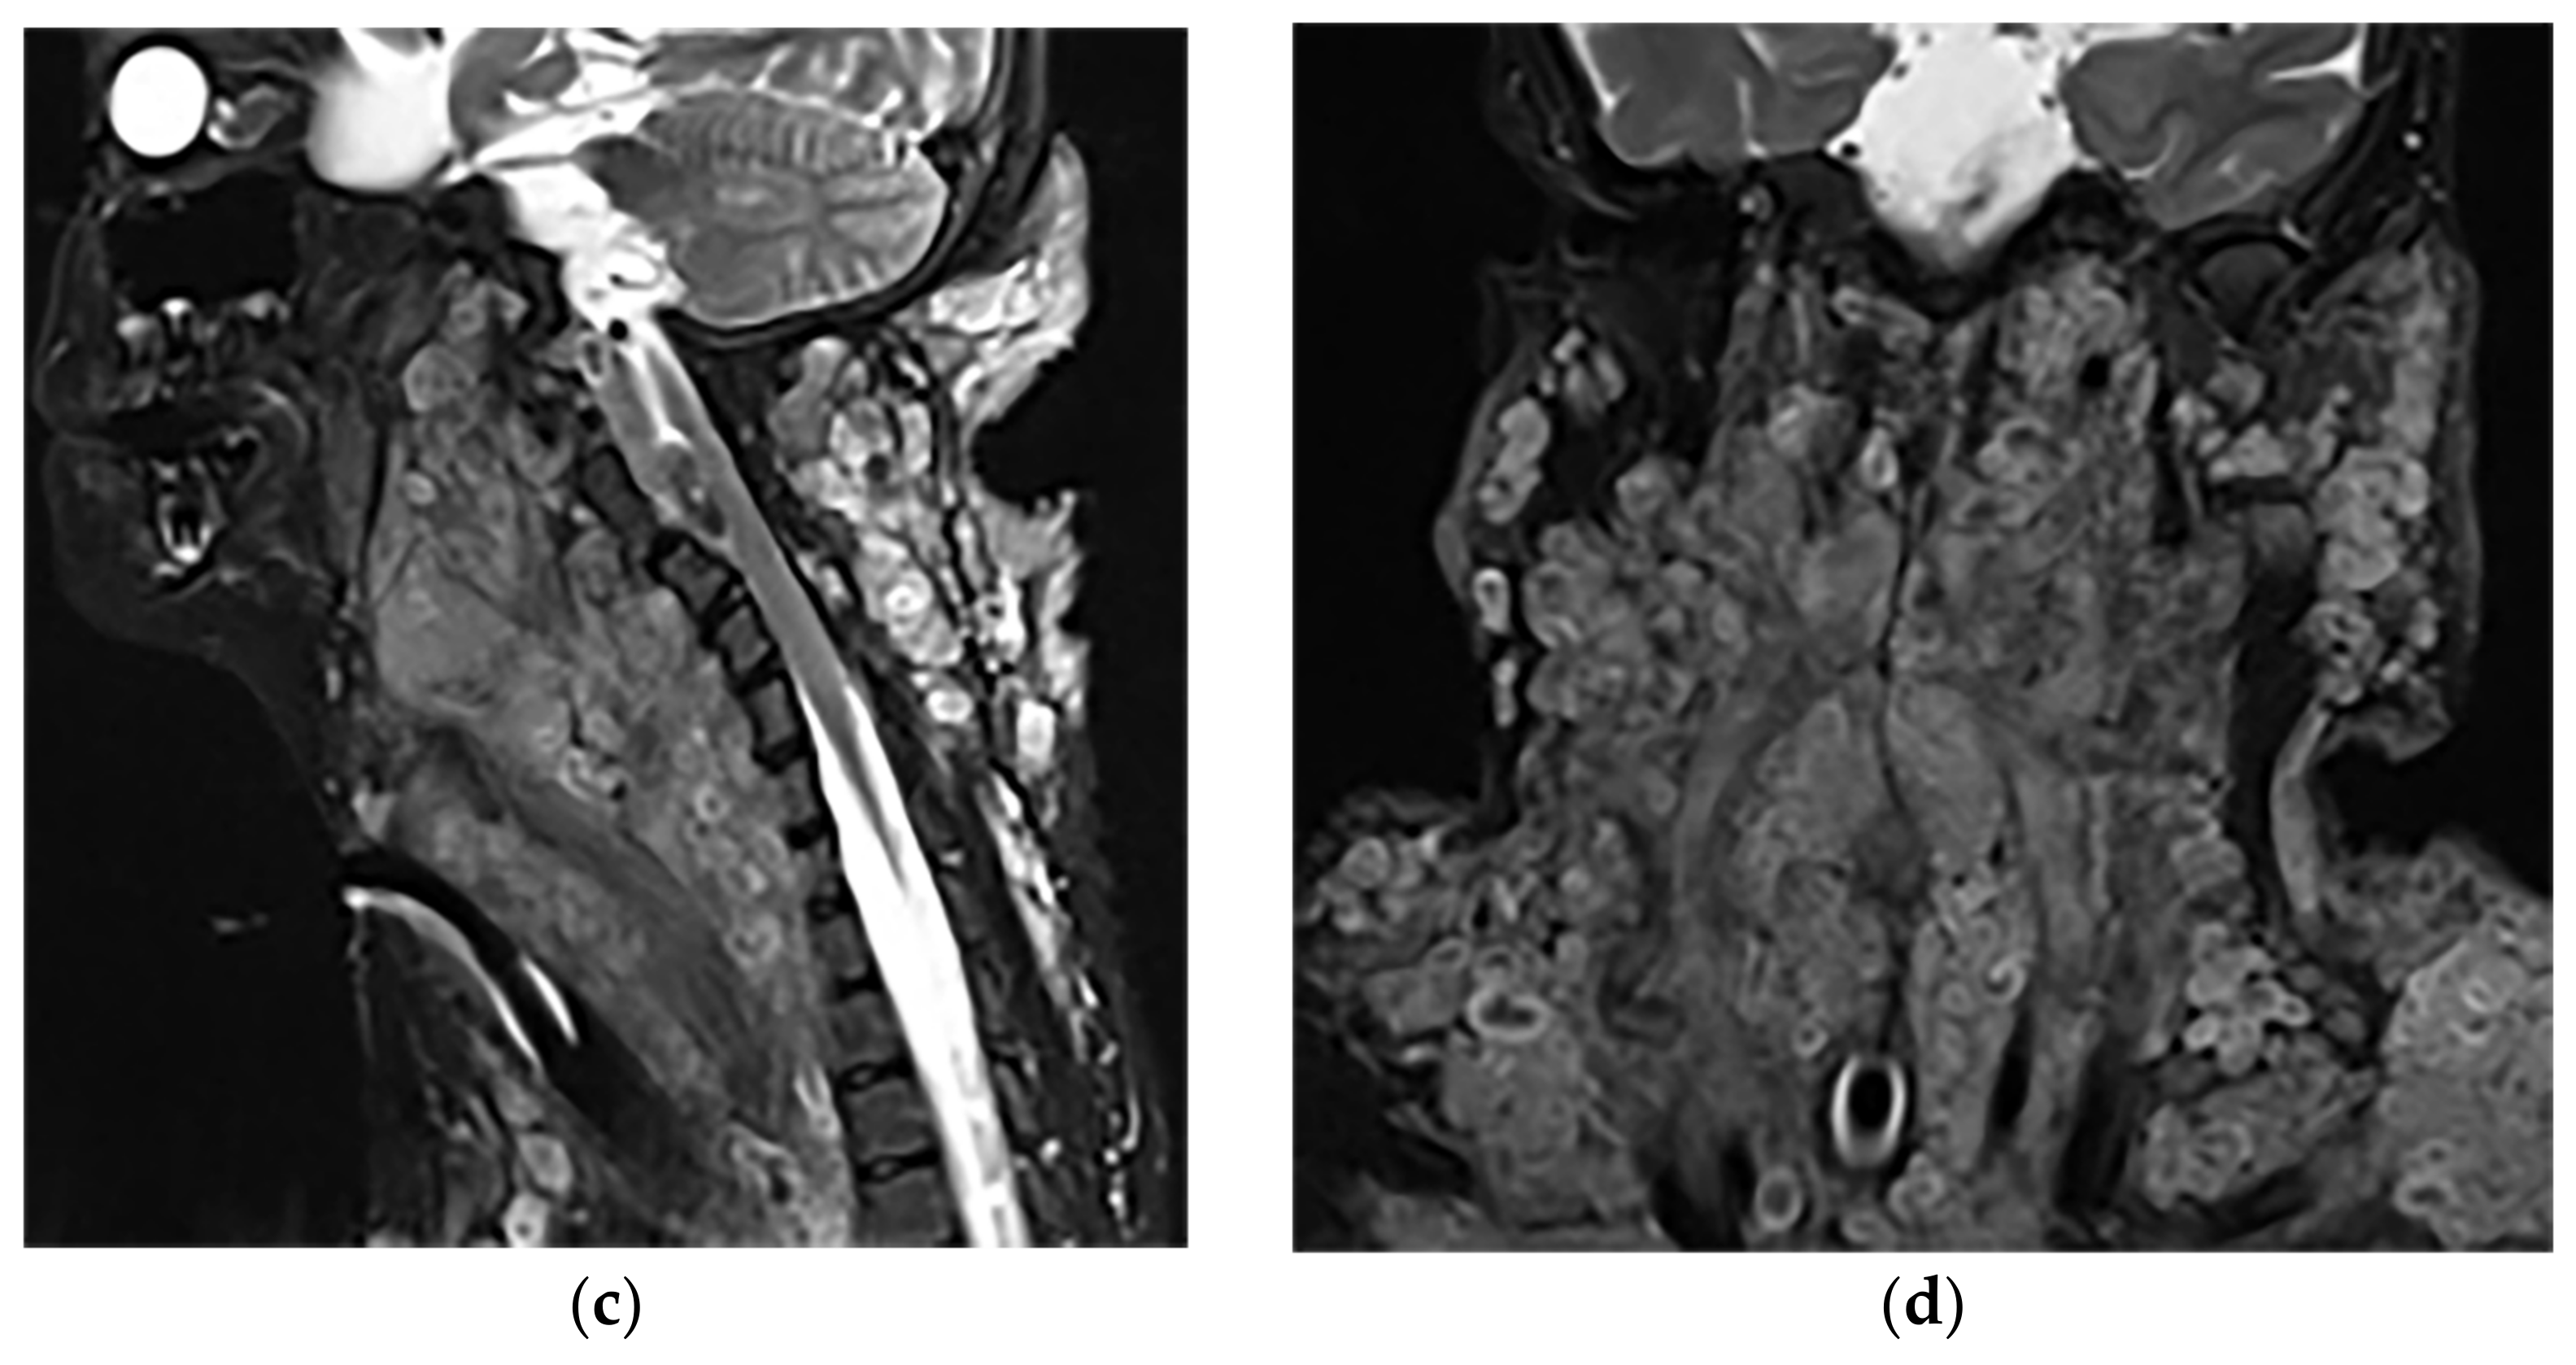

- Kumar, Y.; Gupta, N.; Chhabra, A.; Fukuda, T.; Soni, N.; Hayashi, D. Magnetic resonance imaging of bacterial and tuberculous spondylodiscitis with associated complications and non-infectious spinal pathology mimicking infections: A pictorial review. BMC Musculoskelet. Disord. 2017, 18, 244. [Google Scholar] [CrossRef]

- Hong, S.H.; Choi, J.-Y.; Lee, J.W.; Kim, N.R.; Choi, J.-A.; Kang, H.S. MR Imaging Assessment of the Spine: Infection or an Imitation? Radiographics 2009, 29, 599–612. [Google Scholar] [CrossRef]

- Ramadani, N.; Dedushi, K.; Kabashi, S.; Mucaj, S. Radiologic Diagnosis of Spondylodiscitis, Role of Magnetic Resonance. Acta Inf. Med. 2017, 25, 54–57. [Google Scholar] [CrossRef]